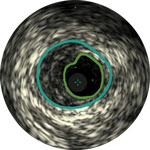

Die IVUS-Technologie von Philips liefert detaillierte Läsionsbilder, die Ihnen die Entscheidung über das optimale Vorgehen erleichtern.

Lumen

Exzentrische fibröse Plaque mit tiefliegendem Calcium

Schallschatten

Erleichtert die Dimensionierung des Geräts, um eine präzise Wandapposition, Medikamentengabe und Platzierung sicherzustellen

Verstehen Sie Art und Schweregrad der Plaque, um das richtige Gerät zu wählen

Visualisieren Sie die Position der Plaque für eine präzise Behandlung

Bestätigen Sie die Position des wahren Lumens oder des subintimalen Führungsdrahts